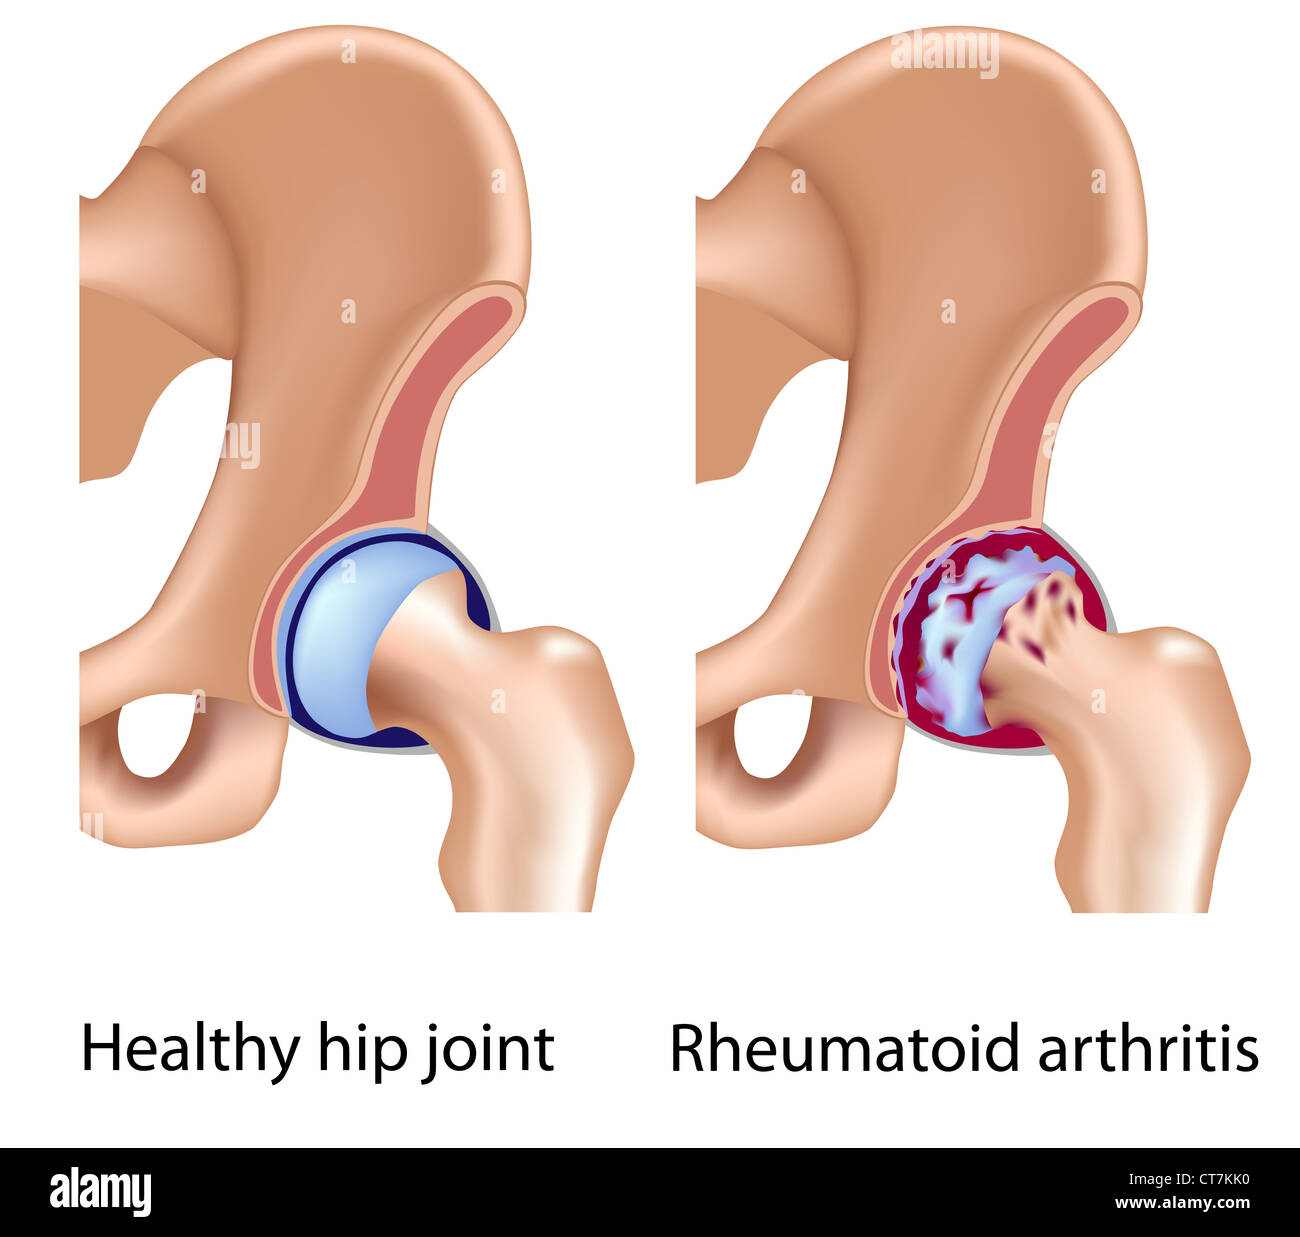

Rheumatoid arthritis of hip joint Stock Photohttps://www.alamy.com/image-license-details/?v=1https://www.alamy.com/stock-photo-rheumatoid-arthritis-of-hip-joint-49341572.html

Rheumatoid arthritis of hip joint Stock Photohttps://www.alamy.com/image-license-details/?v=1https://www.alamy.com/stock-photo-rheumatoid-arthritis-of-hip-joint-49341572.htmlRFCT7KK0–Rheumatoid arthritis of hip joint